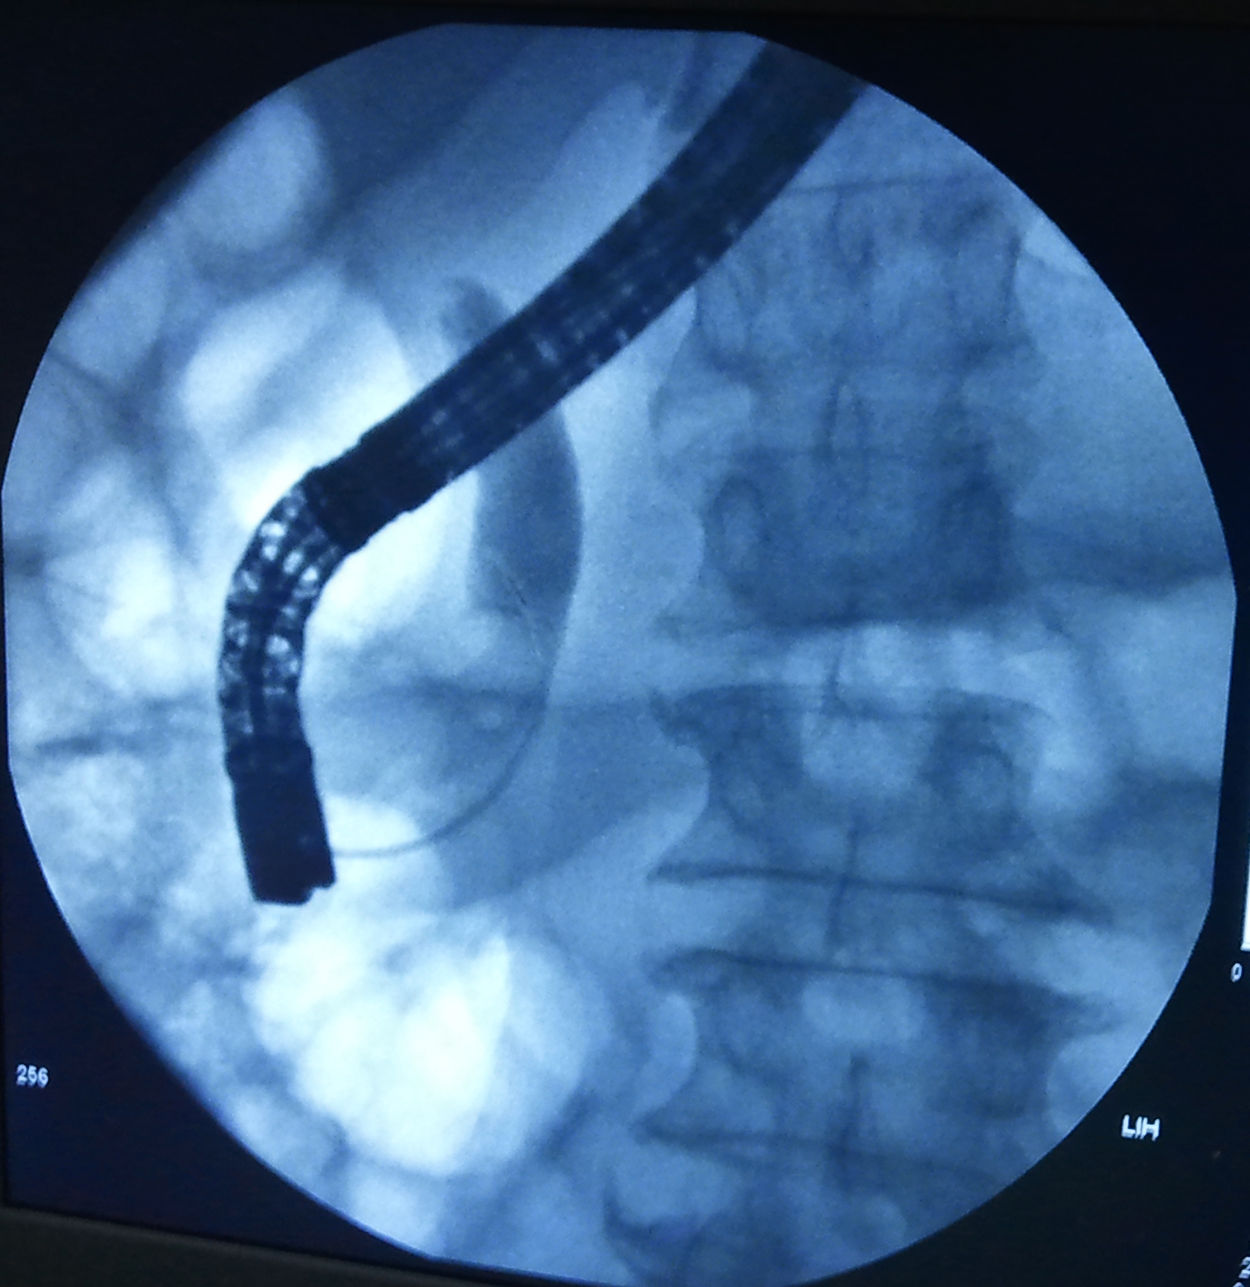

导管通过胆管病变区造影,胆总管中段肿瘤侵犯不显影,远侧造影剂顺利

术中胆管造影显示肝内胆管和胆总管上段严重扩张,胆总管中段胆管占位

术中造影示胆总管中段显影中断,胆总管上段,肝内胆管及胆囊扩张明显